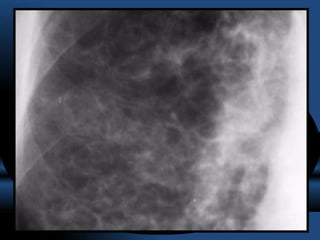

TOMOGRAFIA COMPUTARIZADA DE ALTA RESOLUCION

= GOLD STANDARD

- El diagnóstico se confirma mediante la tomografía computarizada de alta

resolución (TACAR) torácica, que es la exploración con mayor sensibilidad

(96%) y especificidad (93%) en la detección de bronquiectasias y en la

valoración de su evolución.